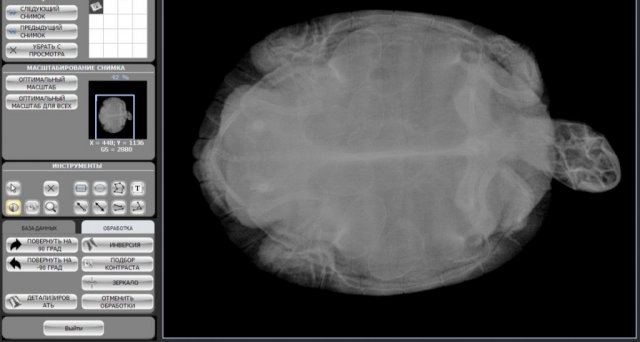

Катран Ваше имя: Елена Локация: Россия Опубликовано: 19 апреля 2024 Автор Опубликовано: 19 апреля 2024 @moth рентген сделали, но он не как на картинках

Консультанты moth Ваше имя: Мария Локация: Москва Опубликовано: 19 апреля 2024 Консультанты Опубликовано: 19 апреля 2024 @MirVam полная шкатулка яиц = ) тут только ждать пока снесётся